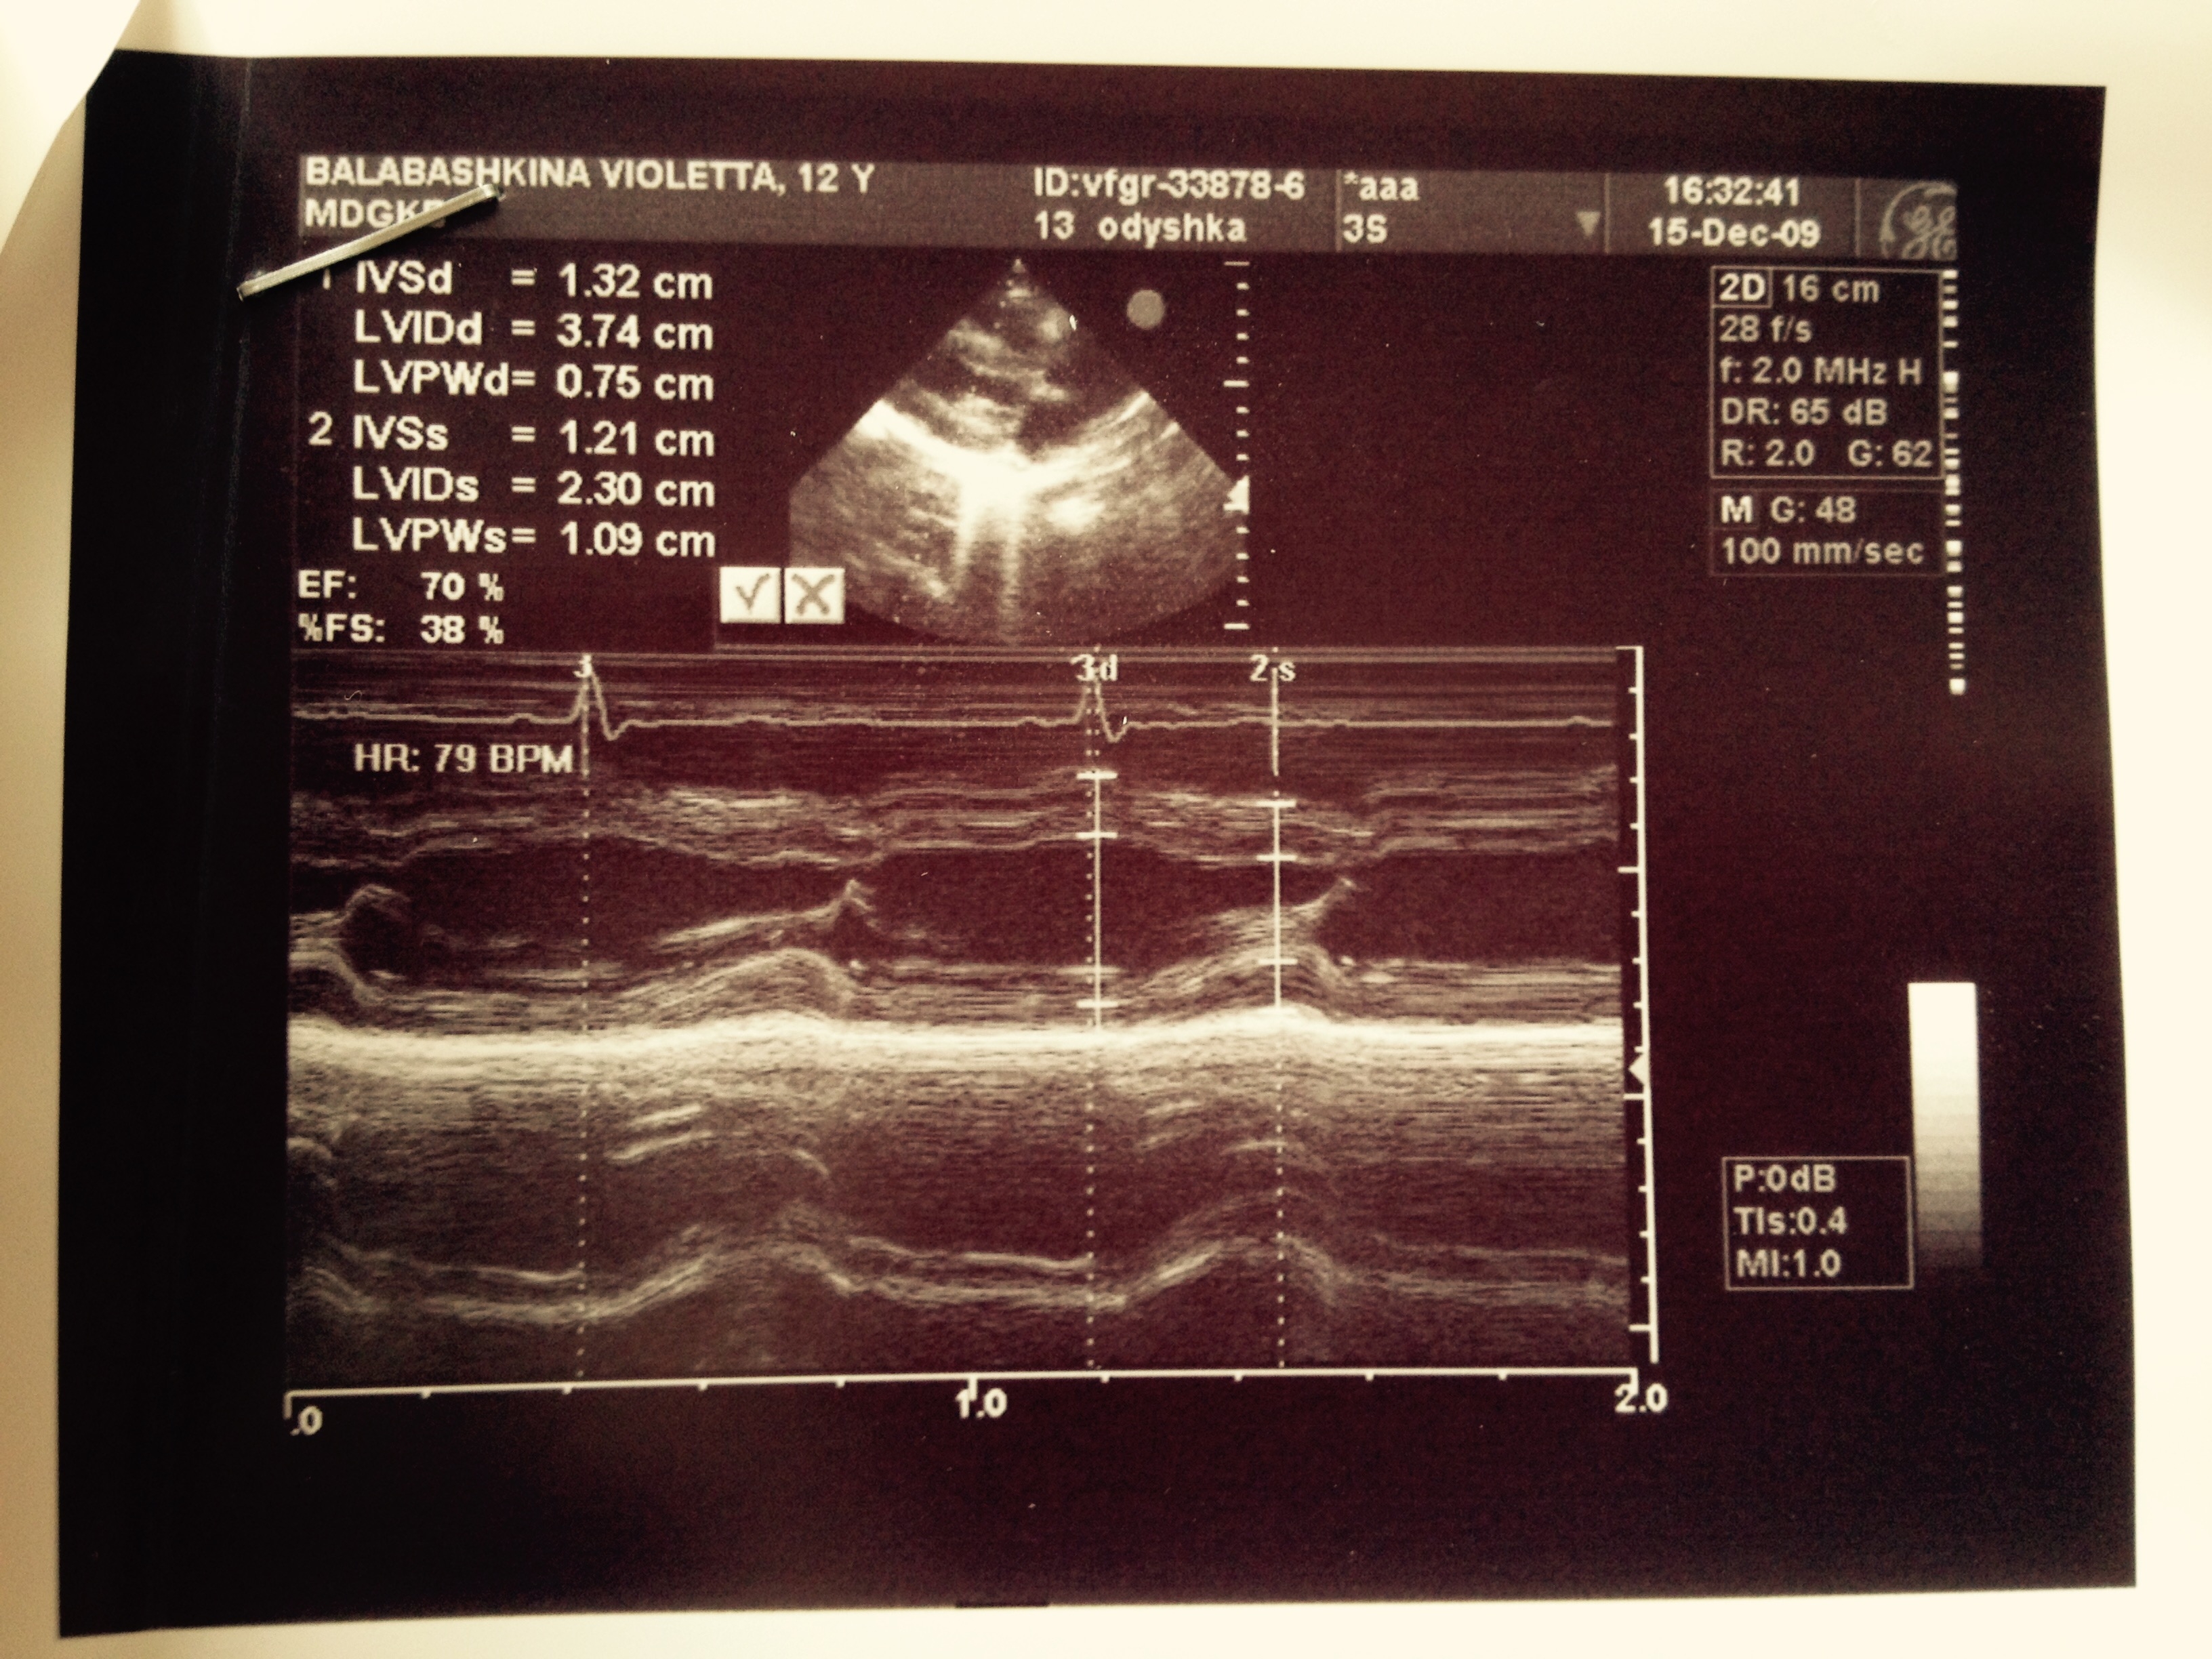

При подробном сборе анамнеза у мамы и, главное, разговоре с девочкой было выяснено, что накануне госпитализации в Измайловскую больницу на фоне психотравмирующего фактора (ссора с подругой) пациентка приняла большое количество таблеток аспирина (количество точно не помнит, более 10). Именно после этого появились выраженные вялость, шум в ушах, многократная рвота (от родителей скрыла), затруднения дыхания, с которыми пациентка была госпитализирована в Измайловскую больницу. При клинико-лабораторном наблюдении в Морозовской больнице — состояние средней тяжести, дыхательная недостаточность 1-й степени, клинико-лабораторных данных за манифестный СД не выявлено (гликированный гемоглобин 5,4%, гликемия в динамике от 3 до 6,7 ммоль/л, кетонемия — отрицательна, аглюкозурия), общий анализ крови — без патологии. Обращали на себя внимание тахипноэ до 36 в минуту, тахикардия до 90—100 в минуту, легкая смешанная одышка при нагрузке в отсутствие нарушений в биохимии крови, в том числе электролитных, выраженный систолический шум на верхушке в отсутствие изменений на ЭКГ. При УЗИ сердца выявлены редкие экстрасистолы со снижением гемодинамической эффективности. Заключение невролога: мелкоразмашистый горизонтальный и вертикальный нистагм.

1. УЗИ сердца пациентки | |